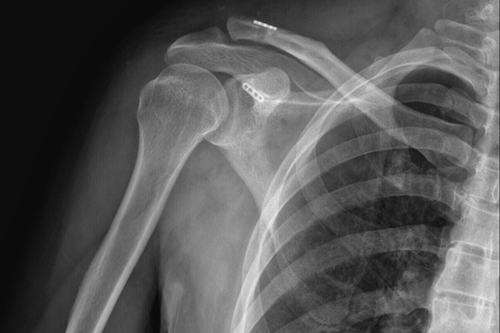

术后DR

传统手术术后DR

一名50岁的男性患者,因不慎摔伤致右肩关节肿痛,并伴活动受限4天后来附院求治。入院查体发现患者右肩部肿胀明显,右锁骨远端隆起畸形,局部明显按压出现疼痛,肩部外展活动受限,进行X线检查显示“右肩锁关节脱位”。骨三科医师团队根据患者病情,进行充分商讨,确定了手术治疗方案,决定为患者实施“右肩锁关脱位复位带袢钢板内固定术”。由副主任医师蒋宇平主刀,骨三科手术团队在患者锁骨上方及喙突处各取2cm手术切口,将肩锁关节复位后,使用瞄准器由喙突基底部向锁骨远端建立骨性隧道,最后将带袢钢板由骨道穿出后固定,术中出血仅10ml左右。

骨三科主任朱述浪表示,近年来,随着生活水平的提高,患者对手术方式、手术效果的心理预期也不断提高。传统手术通过使用锁骨钩钢板来治疗肩锁关节脱位,其固定方式虽牢靠,但手术切口较大,术后极易出现脱钩、肩峰撞击,下骨溶解甚至造成骨折,疼痛发生率非常高,同时,内固定需2次手术拆除,且拆除后存在再脱位的可能。相比之下,带袢钢板内固定术能够有效恢复肩锁关节各方向的稳定性,不但符合肩锁关节生物学特性,还能最大程度地减少患者的创伤,并尽可能达到美容效果。该手术的开展,有望为广大患者提供更安全、更人性化的医疗服务。